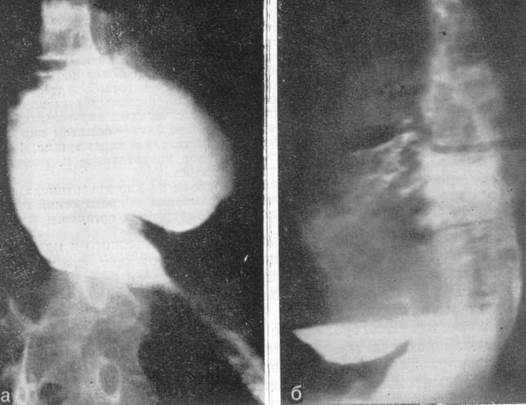

Ведущим методом исследования является многоплоскостное рентгенологическое исследование. Оно позволяет выявить размеры и форму тела дивертикула, длину и ширину, угол перегиба шейки, признаки дивертикулита (рис.2,3).

Рис.2. Рентгенограмма. Крупный (Ценкеровский) пограничный дивертикул с узкой шейкой и дивертикулит.

Рис.3. Рентгенограмма. Длительный (более 6 ч) застой бария в дивертикуле Ценкера.